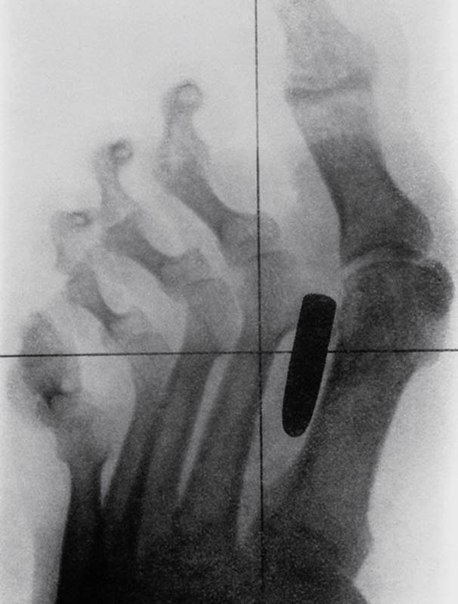

Самые причудливые рентгеновские снимки в истории медицины. Некоторые из них жуткие и пугающие, возможно часть из них вызовет у вас шок. Трудно поверить в то, что это правда, однако снимки говорят сами за себя.. 1) Череп китайского мужчины, который был уби8 写真